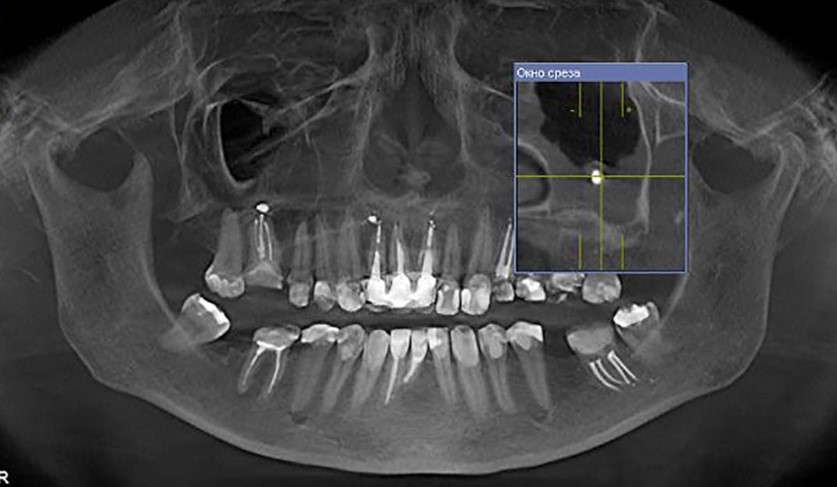

Этот курс был разработан специально для стоматологов, которые хотят уверенно работать с цифровыми технологиями. За 3 вебинара вы пройдёте путь от основ навигации и моделирования шаблонов до планирования тотальных реабилитаций и разбора хирургического протокола с клиническими примерами.

Этот курс был разработан специально для стоматологов, которые хотят уверенно работать с цифровыми технологиями. За 3 вебинара вы пройдёте путь от основ навигации и моделирования шаблонов до планирования тотальных реабилитаций и разбора хирургического протокола с клиническими примерами.